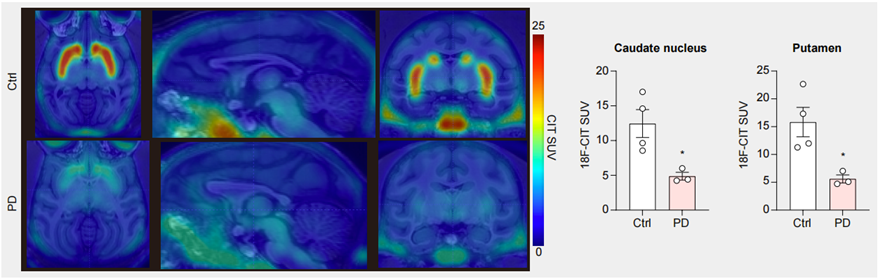

帕金森?。≒D)猴模型

適用于針對PD表型的各類藥物、細胞基因療法、腦機接口等治療手段的臨床前研究。

●  行為學檢測顯示造模后動物出現PD樣行為學表型;

●  分子影像數據展示造模后,動物腦內多巴胺神經元損傷;

●  成模率高,且可以控制模型嚴重程度,PD樣行為學表型穩定持久;

●  給予L-Dopa后,PD樣行為迅速緩解。

圖3. PET-CT結果顯示PD模型猴腦中多巴胺神經元減少